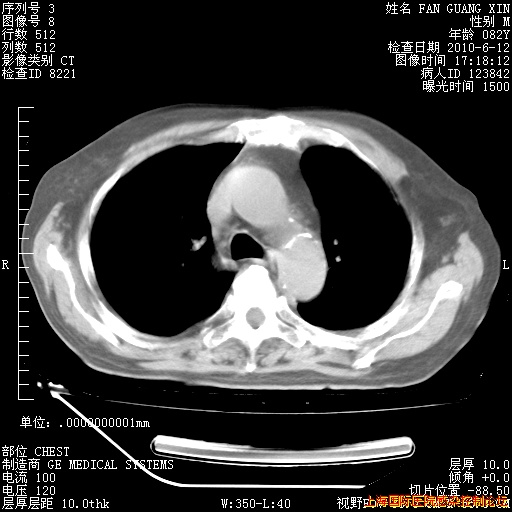

6月12日纵膈窗